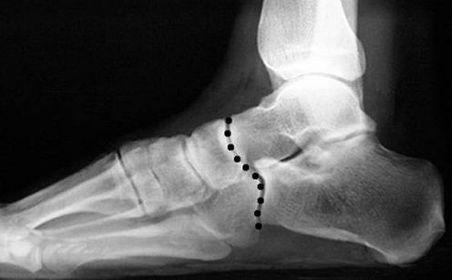

| What is this called? What does an anterior break indicate? What does a posterior break indicate? | Cyma Line/Midtarsal joint. Anterior break = pronated foot type Posterior break = supinated foot type |

| What is this? What foot type is this visible in? | Sinus tarsi/bullet hole sign. Pes cavo-varus |

| What is this? What foot type is this visible in? | Double talar dome sign. Pes cavo-varus |